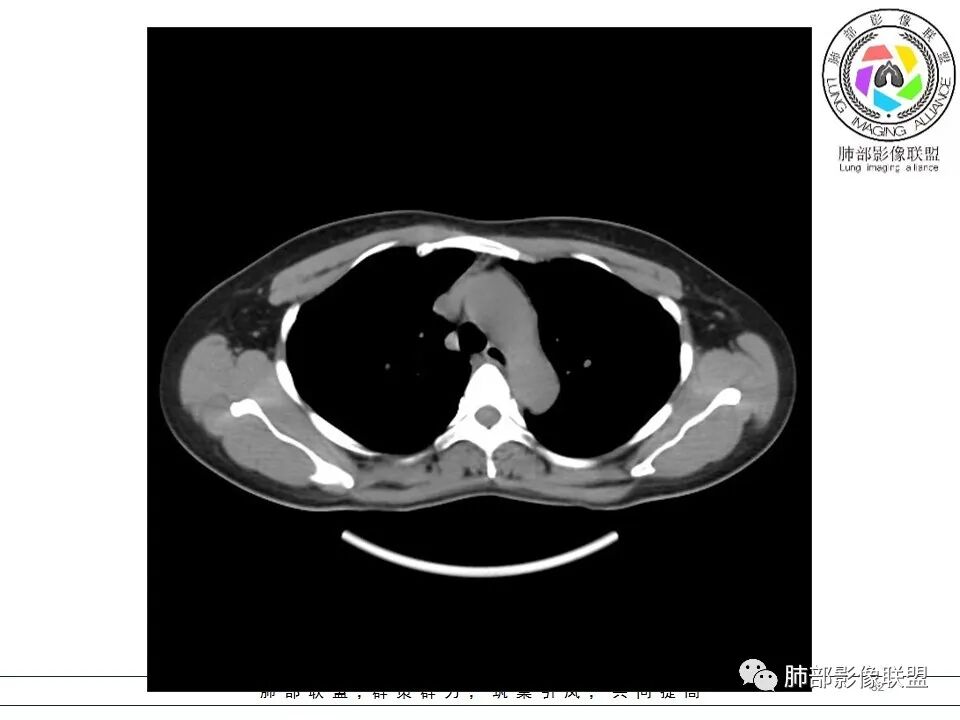

女,38岁,无症状,胸片体检发现两肺可疑病灶。

?其母亲有肺大泡,2017年手术。影像学特点:两肺胸膜下多发的大小不等囊状气腔,壁很薄或无可见的囊壁,小囊的边界比较清楚,大囊的形态比较怪异,以两下肺为著。考虑肺组织细胞增生症,鉴别肺淋巴管肌瘤病。

其母亲有肺大泡,2017年手术。

BHD主要影像表现特征:    1、两肺内肺囊肿:80%以上的BHD患者会出现肺内囊肿,且倾向于基底部近胸膜下分布,特别是纵膈侧肺膜下,囊肿形状不规则、囊肿可大可小,肺内囊肿多毗邻肺下动脉或静脉近端,胸部CT上囊肿分布和特点对诊断有提示意义。    2、继发自发性气胸:BHD患者发生气胸风险是正常人的5倍,BHD患者的气胸发生率约为 1/4,气胸复发率则高达59%。   3、肾肿瘤:(常为双侧性、倾向于嫌色细胞组织学亚型)   4、皮肤表现(为面、颈部纤维性毛囊瘤、毛盘瘤)